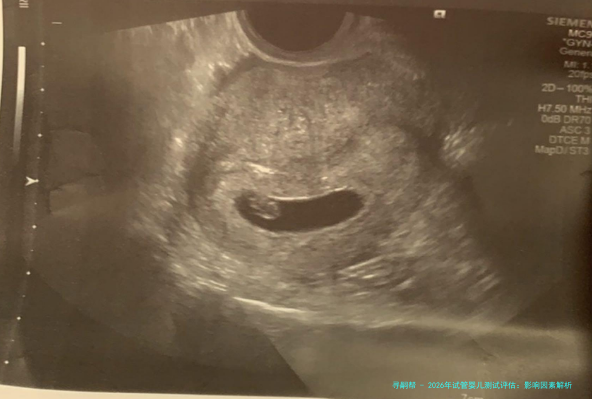

临床妊娠率:指移植后通过B超察看到孕囊的周期比率。这是中期指标。